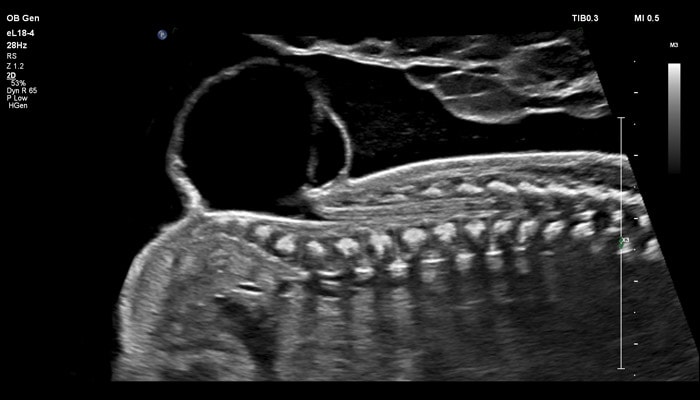

Применение eL18-4 в I триместре беременности

Линейный матричный датчик eL18-4 позволяет получить детальную информацию об анатомии плода и выявить пороки на ранней стадии развития. Сверхширокополосная PureWave матрица датчика генерирует частоты в диапазоне 2-22 МГц, что формирует одинаково высокоинформативные, четкие изображения по всей глубине сканирования до 14 см.

Высокочастотный датчик Philips eL18-4 содержит решетку из 1920 активных монокристаллических пьезоэлементов, выполненных по усовершенствованной технологии PureWave. Это обеспечивает высокодетальную 2D визуализацию, которая в совокупности с глубиной сканирования необходима для уверенной диагностики в акушерстве.

Использование линейного матричного датчика eL18-4 при осмотре беременных в I триместре, особенно на ранних сроках, позволяет ограничиться трансабдоминальным сканированием вместо трансвагинального и при этом получить максимально полную диагностическую информацию. Отсутствие полостного исследования чрезвычайно важно для соблюдения принципа ALARA – использования минимальной необходимой мощности для безопасности пациента. Благодаря применению мультичастотного датчика с диапазоном от 2 до 22 МГц через переднюю брюшную стенку хорошо определяется эмбрион длиной 3 мм, что соответствует шестой неделе беременности. В конце I триместра с eL18-4 достаточно отчётливо визуализируется четырёхкамерный срез сердца, мочевой пузырь и сосуды пуповины, которые, как правило, определяются только при трансвагинальном сканировании.

Во II триместре беременности высокая разрешающая способность eL18-4 позволяет детально изучить структуру органов и тканей и увидеть многие нюансы, которые при работе другими датчиками не обнаруживались или становились очевидны в более поздние сроки. Например, у 19-недельного плода визуализируется перегородка носа, мышцы языка, диафрагма между грудной и брюшной полостью, на 20-й неделе чётко определяются оболочки спинного мозга и уретра, а на 24-й – хорошо дифференцируются корень лёгкого, борозды и извилины мозжечка и многие другие структуры.